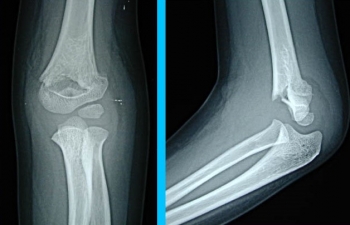

肘の病気、第7回目は上腕骨顆上骨折です。

上腕骨顆上骨折

上腕骨顆上骨折は、上腕骨の遠位端部分(肘の近く)の骨折です。

上腕骨顆上骨折の診断

X線写真が必要です

上腕骨内顆骨折、上腕骨外顆骨折など、類似した骨折もありますし、骨折の折れ方も程度がありますので、必ずX線写真を撮ってください